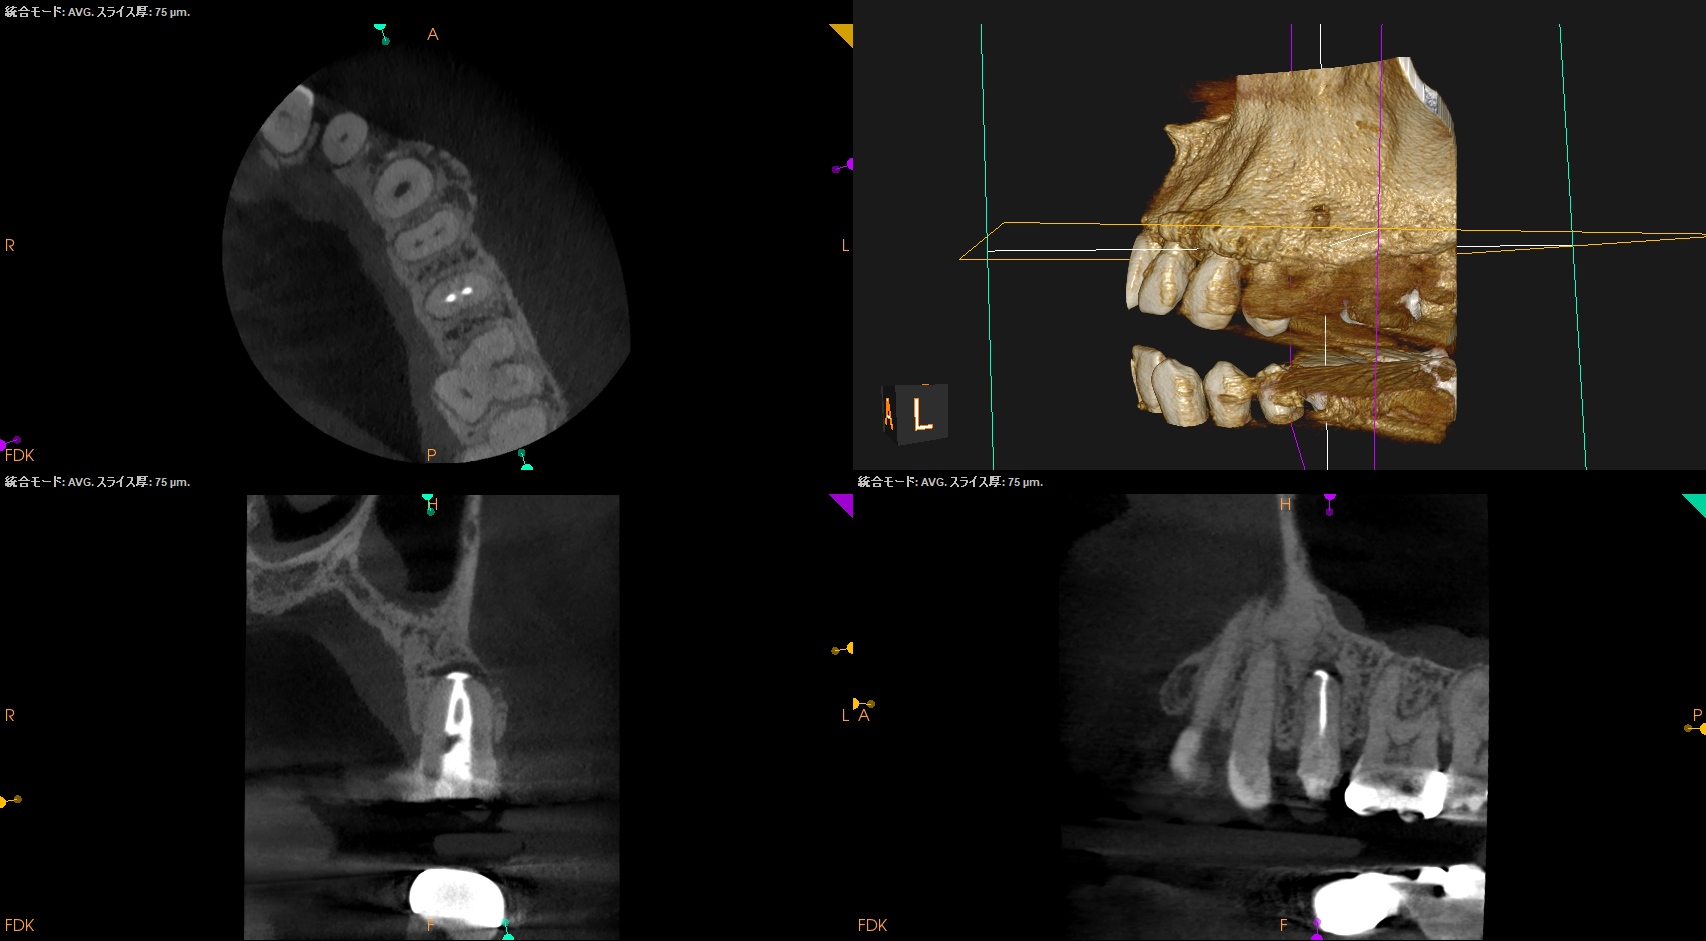

#13 RCT 1yr recall(2026.2.26)

1年前と比較した。

根尖病変は大きく縮小し、臨床症状(圧痛)も消失したのでかかりつけ医の先生には最終補綴を依頼した。

次回はさらに1年後である。

またその予後をお伝えしたい。